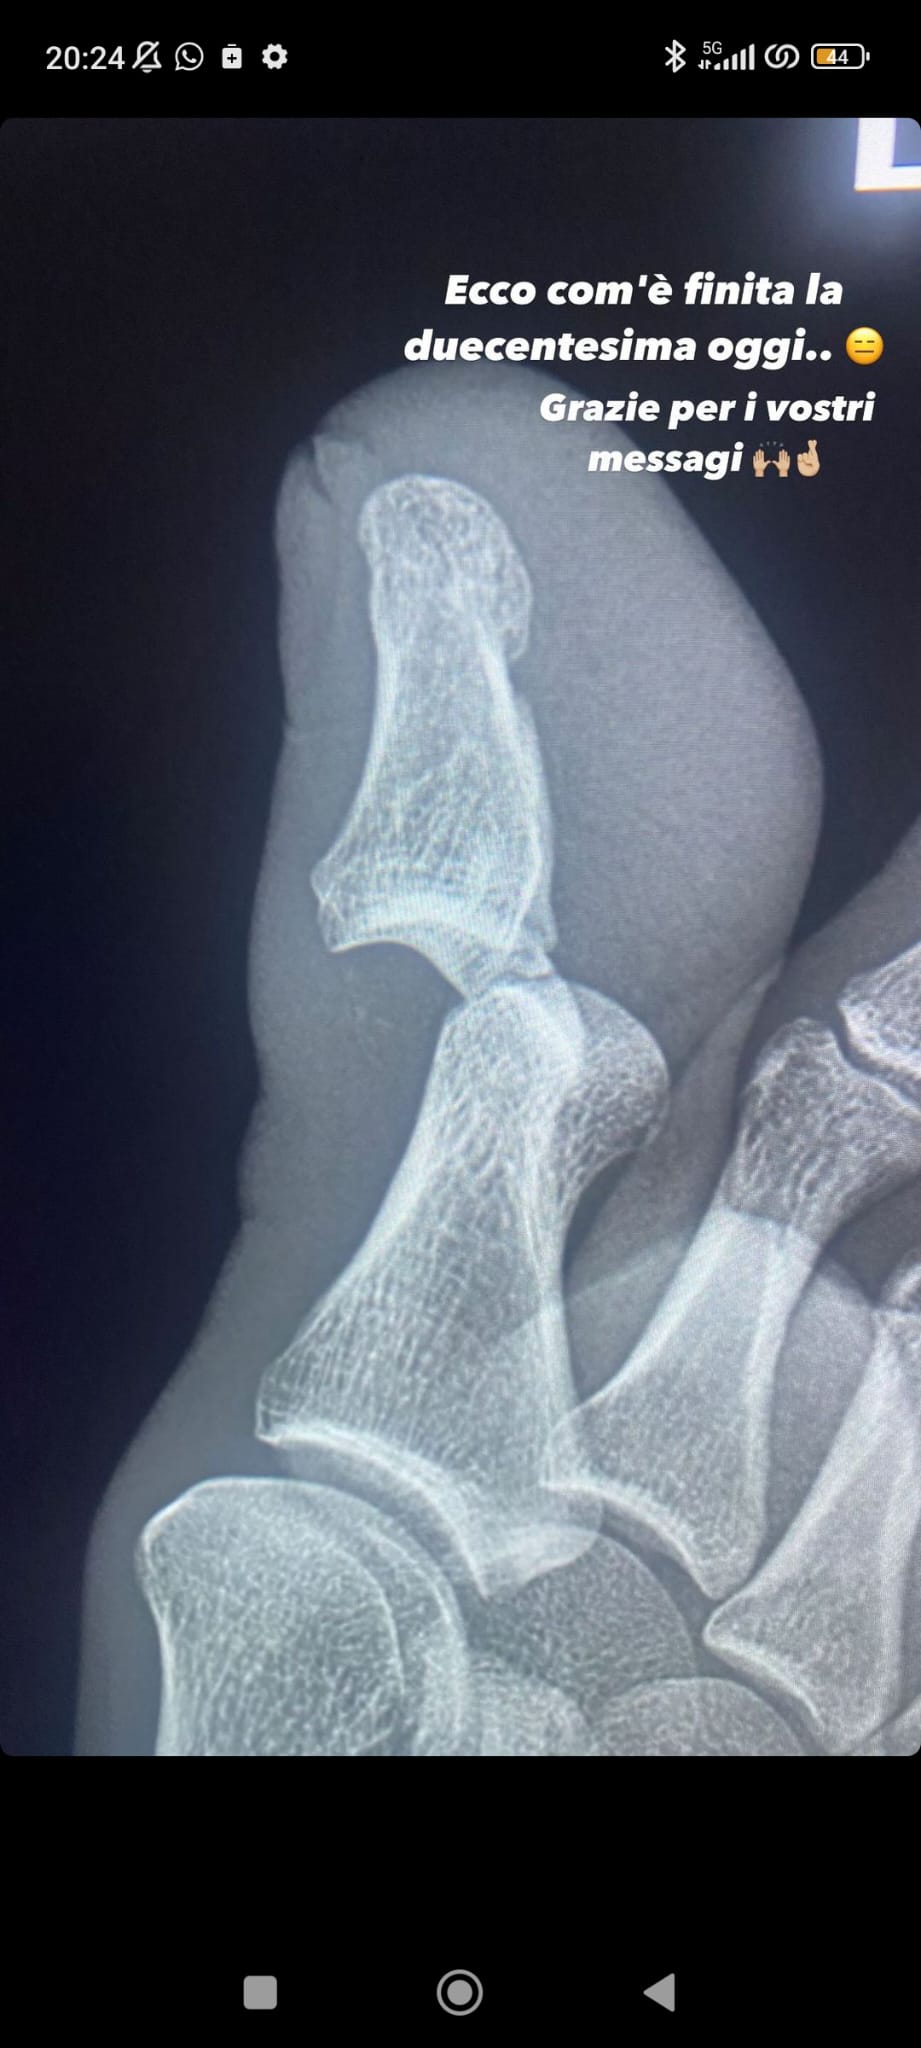

Una duecentesima presenza con la maglia della Juventus senza dubbio non da incorniciare per Adrien Rabiot. Il centrocampista francese, infatti, è stato costretto a lasciare il campo al 29' del primo tempo dopo un contrasto con Bremer che gli ha provocato una lussazione al dito del piede. Lo stesso Rabiot, poi, ha voluto ironizzare il fatto sul suo profilo Instagram, postando un immagine della lastra e ringraziando i tifosi bianconeri per i messaggi di vicinanza

"Ecco com'è finita la duecentisima oggi.... Grazie per i vostri messaggi", ha scritto il centrocampista francese.